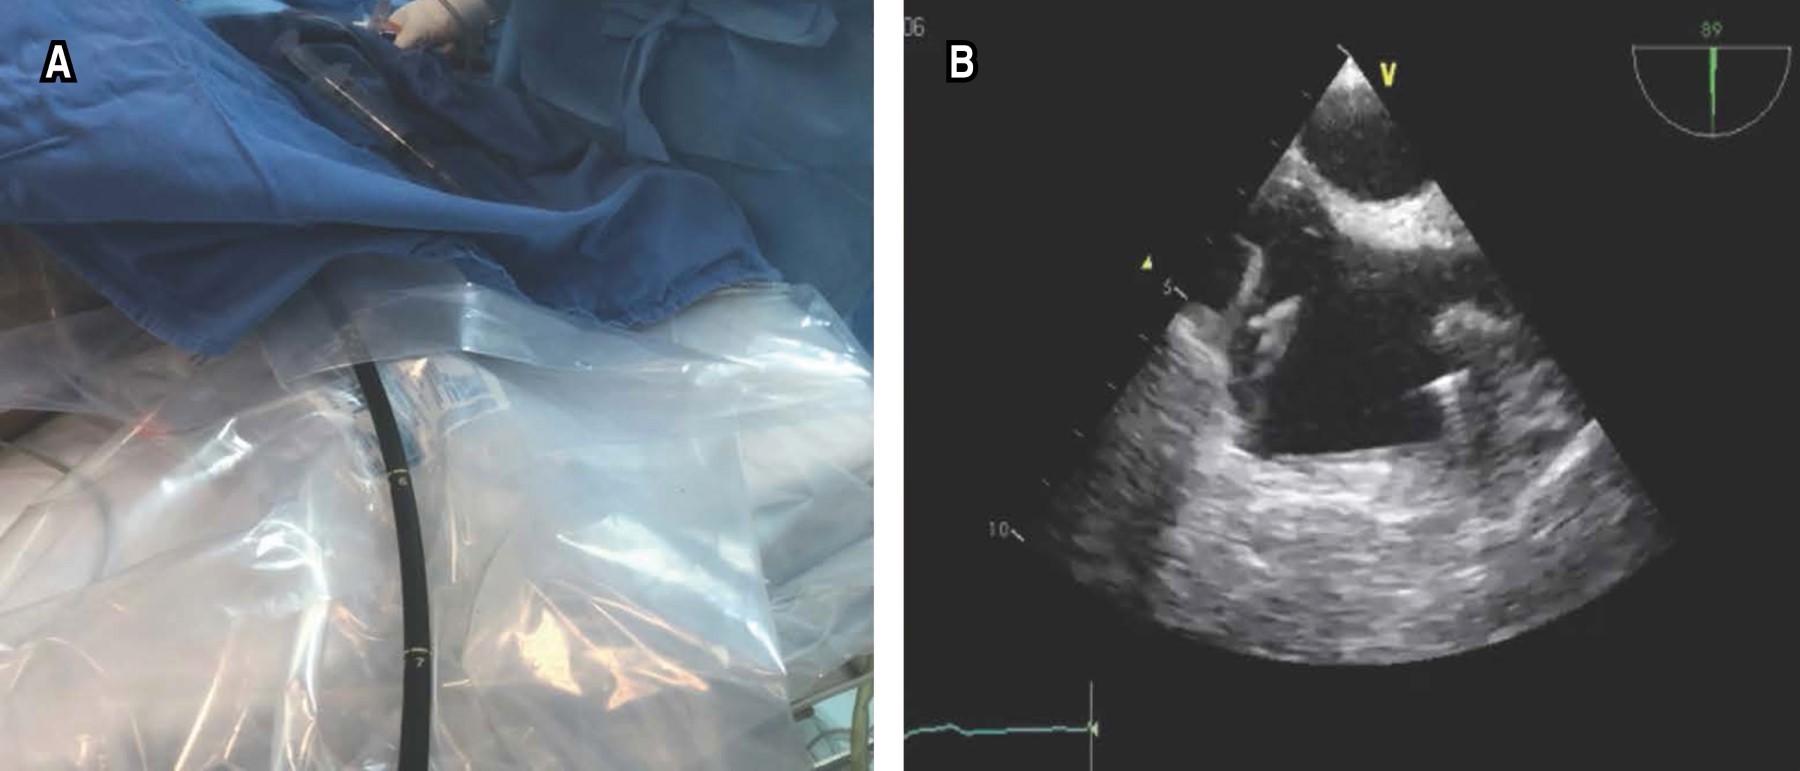

Como primer paso del flujograma (Figura 1), todo el personal debe tener una EPP adecuada y proteger la sonda del ETE (Figura 2A). Después de la sedación intravenosa, se inserta la sonda de ETE, siendo la proyección seleccionada para guiar el procedimiento la vista bicaval esofágica media de 90-110 grados (Figura 2B), donde podemos guiar en tiempo real el posicionamiento correcto de la cánula de retorno (yugular) (Figura 3A), que debe colocarse en la porción media de la aurícula derecha en dirección a la válvula tricúspide. El flujo adecuado puede evaluarse mediante Doppler color (Figura 3B). La sonda de ETE con el mismo grado de angulación se avanza distalmente hacia el esófago para observar la vena cava inferior y la cánula de extracción (femoral) que debe estar separada 8 a 10 cm de la cánula de retorno (Figura 3C y D); esto limita los fenómenos de succión y recirculación.